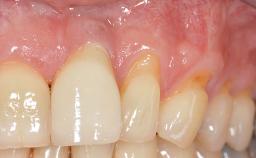

Soft-Tissue Volume Augmentation Using a Connective-Tissue Graft Harvested from the Maxillary Tuberosity

In 1983, a 51-year-old non-smoking patient was referred for the treatment of moderate chronic periodontitis. At the initial examination, 47% of sites exhibited probing depths of 4 to 6 mm. Periodontal therapy consisted of initial periodontal treatment including oral-hygiene instructions and supra- and subgingival debridement, followed by periodontal surgery to eliminate residual pockets.